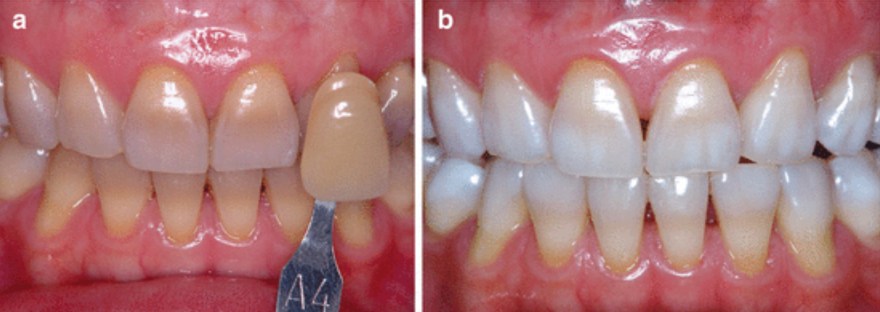

了解與牙周病的發展,也可幫助民眾做簡單的自我檢查,以便早期發現、早期治療。健康的牙齦組織為但淡粉紅色,牙齦結實。一旦牙菌斑累積,初期會引發牙齦炎,此時牙齦外觀紅腫,刷牙時牙齦會出血。當牙齦發炎沒有即時控制治療,牙齦炎將發展至牙周病,病患會發現牙齦明顯退縮、牙縫越來越大、牙齒開始對冷熱酸痛敏感、口臭、牙齒搖動,咀嚼時不如以往紮實有力,甚至會有疼痛感,嚴重者口內會出現化膿現象。